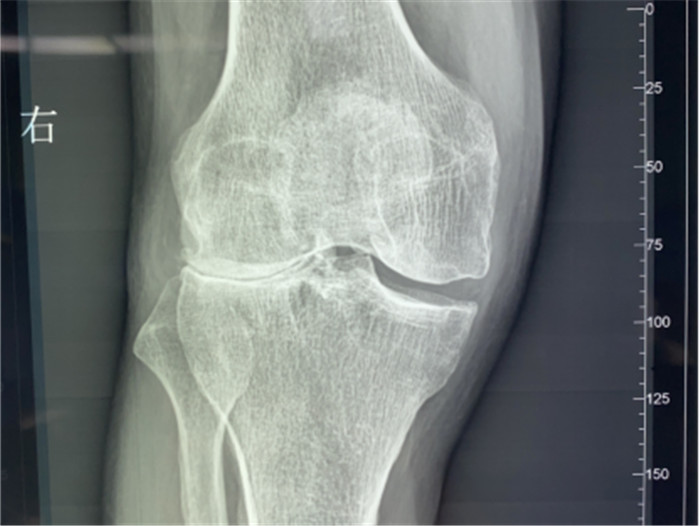

▲右膝關(guān)節(jié)外翻畸形

接診后羅軍主任詳細檢查病人,發(fā)現(xiàn)病人疼痛癥狀主要集中在膝關(guān)節(jié)外側(cè)間室,右下肢有明顯外翻畸形。這些癥狀都是單髁置換的適應(yīng)癥。雙下肢全長攝片和右膝內(nèi)翻、外翻位攝片顯示,膝關(guān)節(jié)外側(cè)間隙消失,膝外翻畸形,果不其然印證了上述臨床表現(xiàn)。收治入院后,羅主任團隊決定為患者實施微創(chuàng)膝關(guān)節(jié)外側(cè)單髁置換術(shù),盡全力為張大爺解除病痛的折磨。